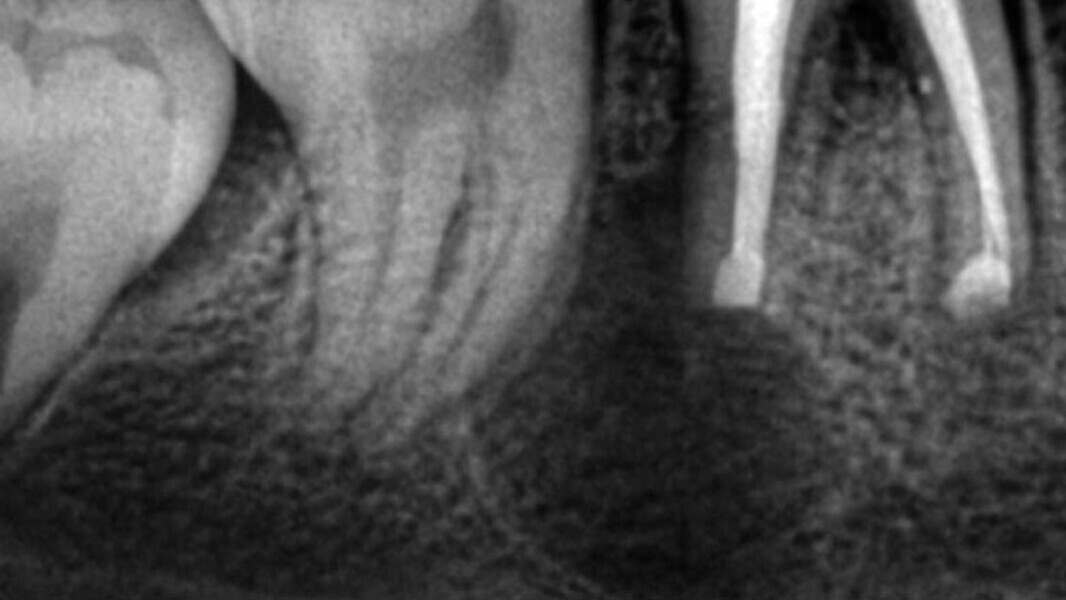

Figura 4. Apicectomía del diente 46.

Figura 5. Preparación apical, sellado y reimplantación.